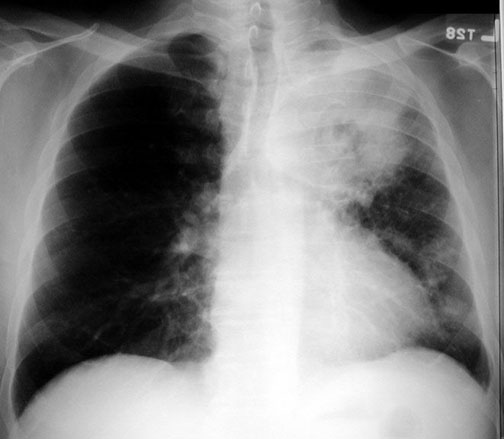

Case 2 Labeled Image What is the differential for multiple cavities?